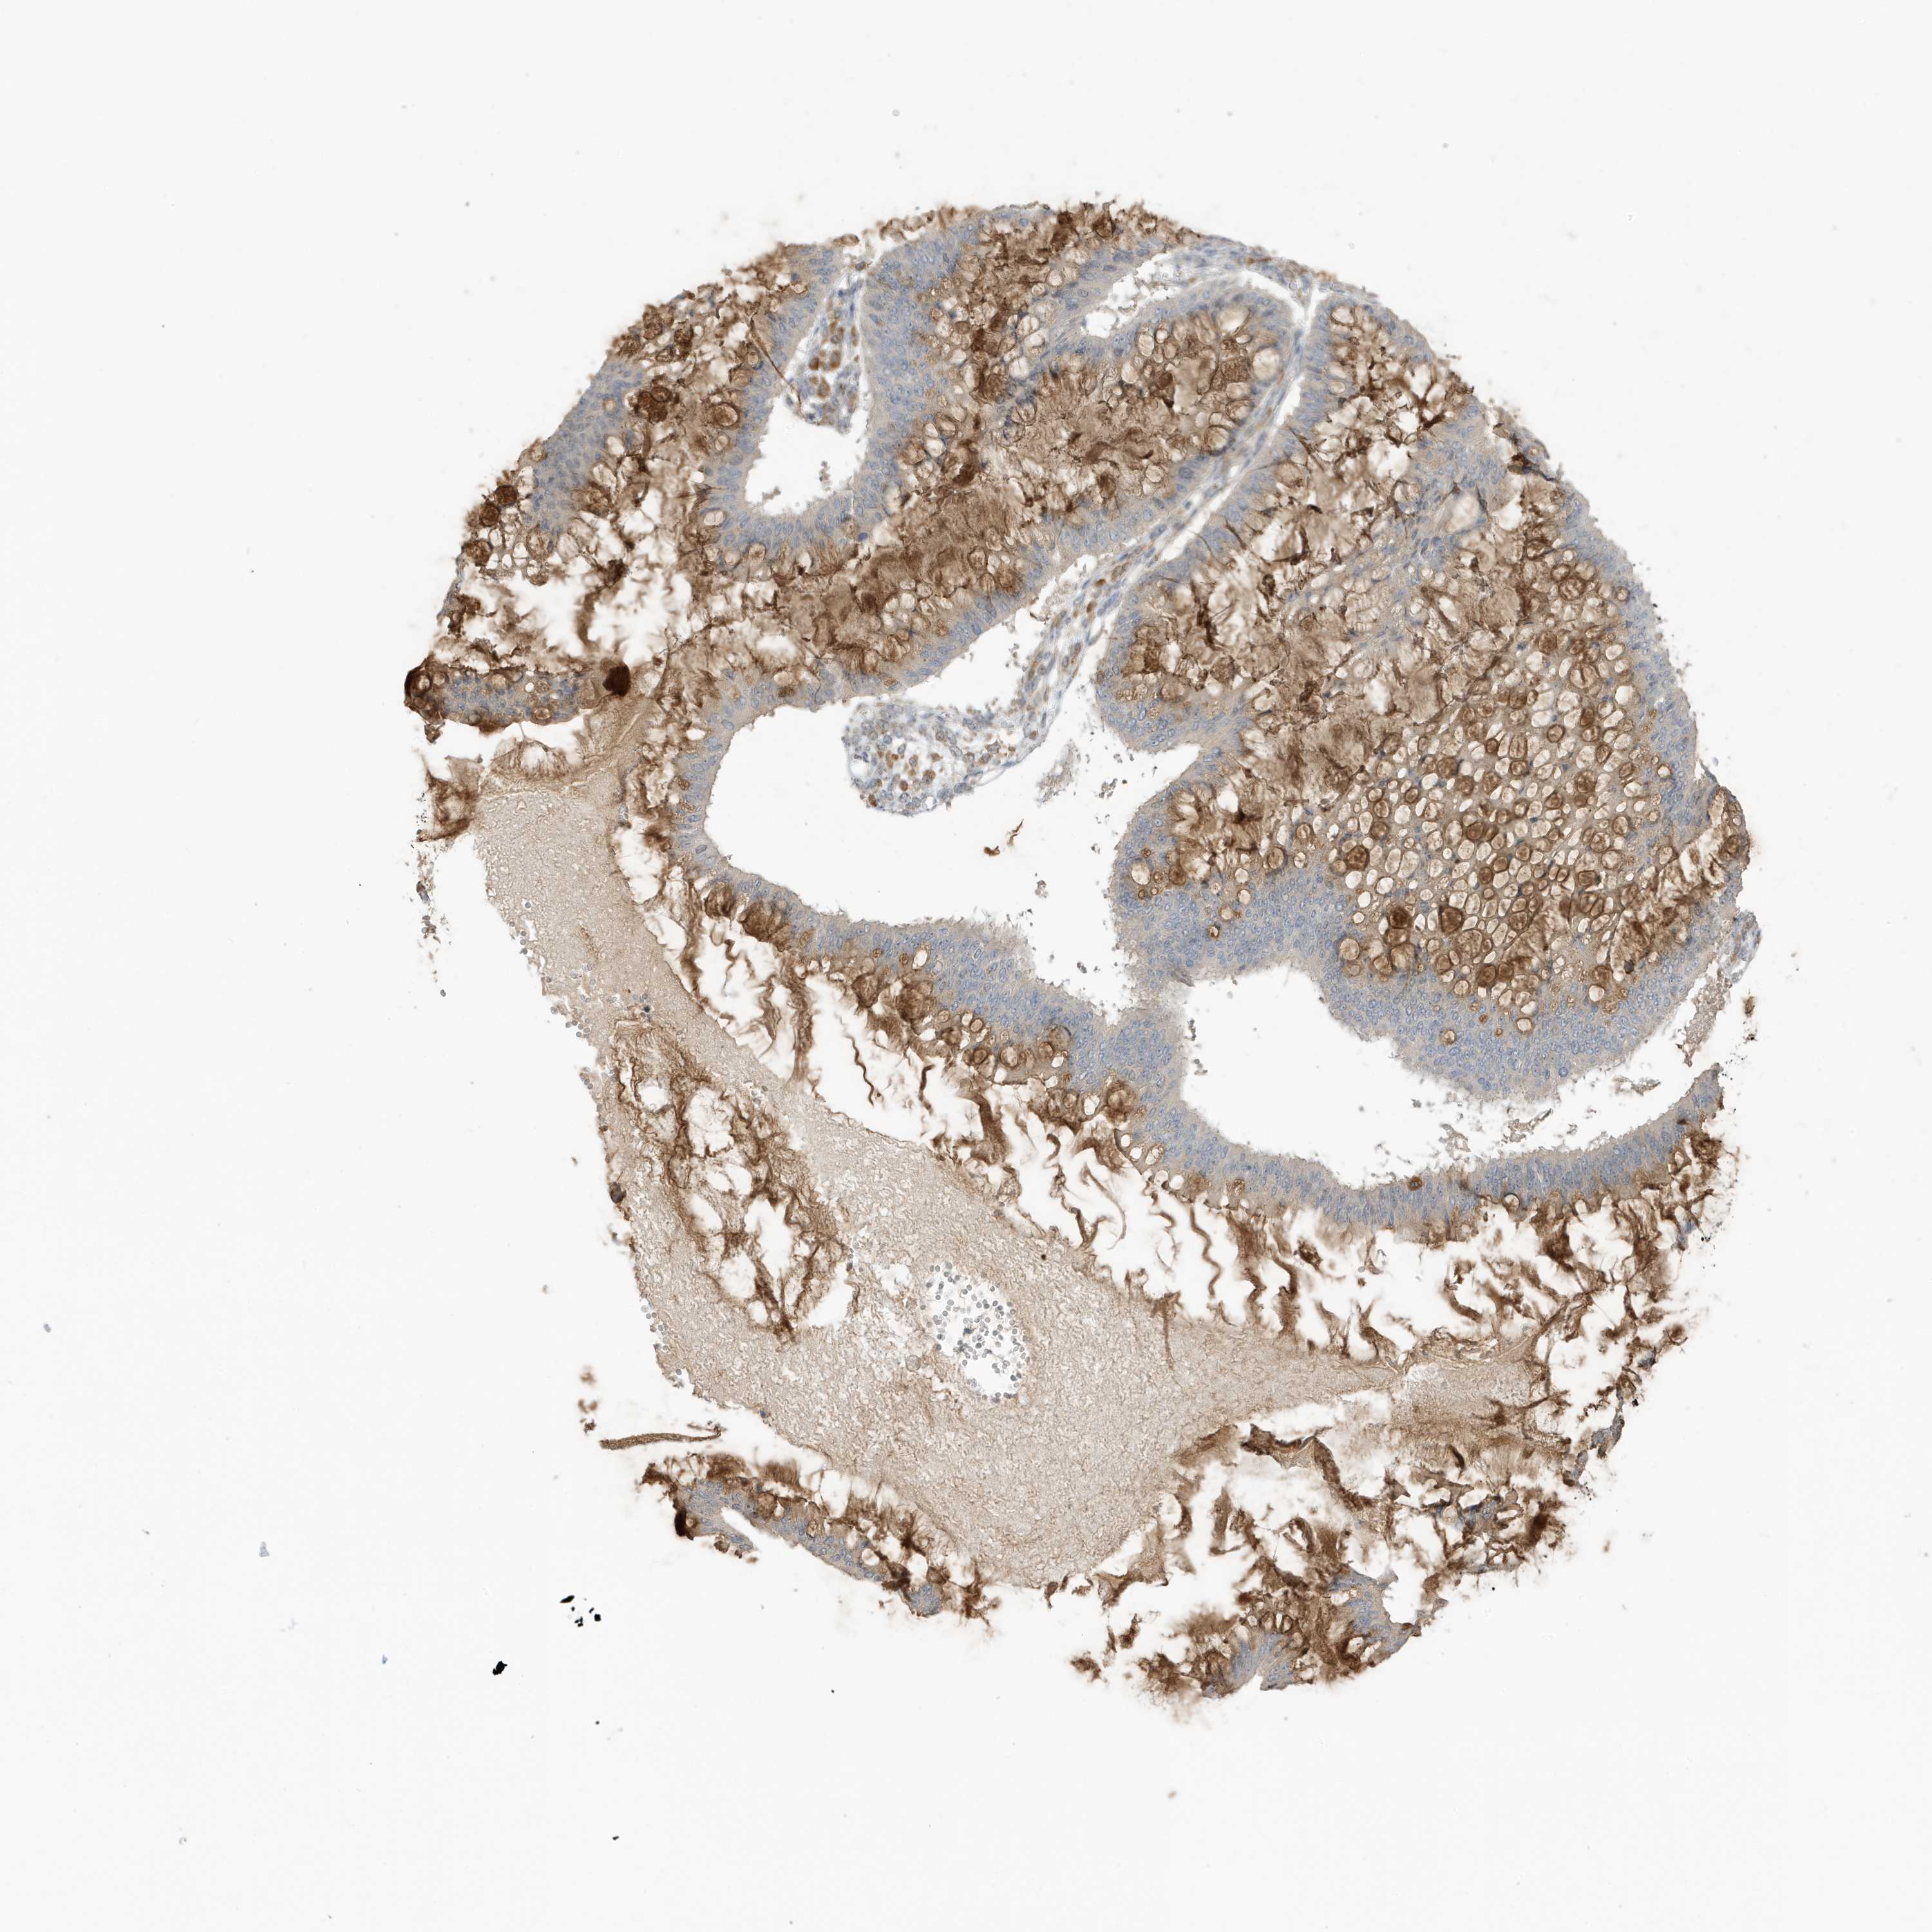

OVARIAN CANCER - Protein expressioni

A mouse-over function shows sample information and annotation data. Click on an image to view it in a full screen mode. Samples can be filtered based on level of antibody staining by selecting one or several of the following categories: high, medium, low and not detected. The assay and annotation is described here.

Note that samples used for immunohistochemistry by the Human Protein Atlas do not correspond to samples in the TCGA dataset.

Antibody stainingi

Antibody staining in the annotated cell types in the current human tissue is reported as not detected, low, medium, or high, based on conventional immunohistochemistry profiling in selected tissues. This score is based on the combination of the staining intensity and fraction of stained cells.

Each image is clickable and will lead to virtual microscopy that enables deeper exploration of all samples and also displays staining intensity scores, fraction scores and subcellular localization as well as patient and tissue information for each sample.

Antibody HPA034980

Antibody HPA034981

Cystadenocarcinoma, serous, NOS